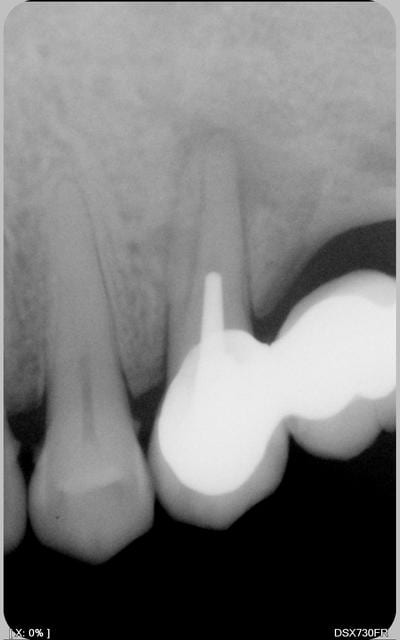

elle vient me voir pour peche sous bridge de 2 ans. section, depose fm re ttmt endo. je la revois dans 3 mois.

jene fais pas confiance a cette dent.

ken pensez vous

Elle est sensible à la percu?

Sinon l'image peut etre due à une racine en forme de 8.

La racine semble effectivement en 8, mais pas de lumière canalaire visible, c'est pour moi le point le plus délicat mais pas infaisable.

On ne voit aucune trace de canal, ni surtout d'obturation. De quoi se demander pourquoi le praticien a fait ça. Je commencerais par le chercher (la racine a la forme d'un cacahuète en section, mais bon, ça arrive). Puisqu'il y a une lésion, il doit exister. Reste à savoir s'il est assez perméable, si pas de fausse route, etc...

la radio.pas de poche paro